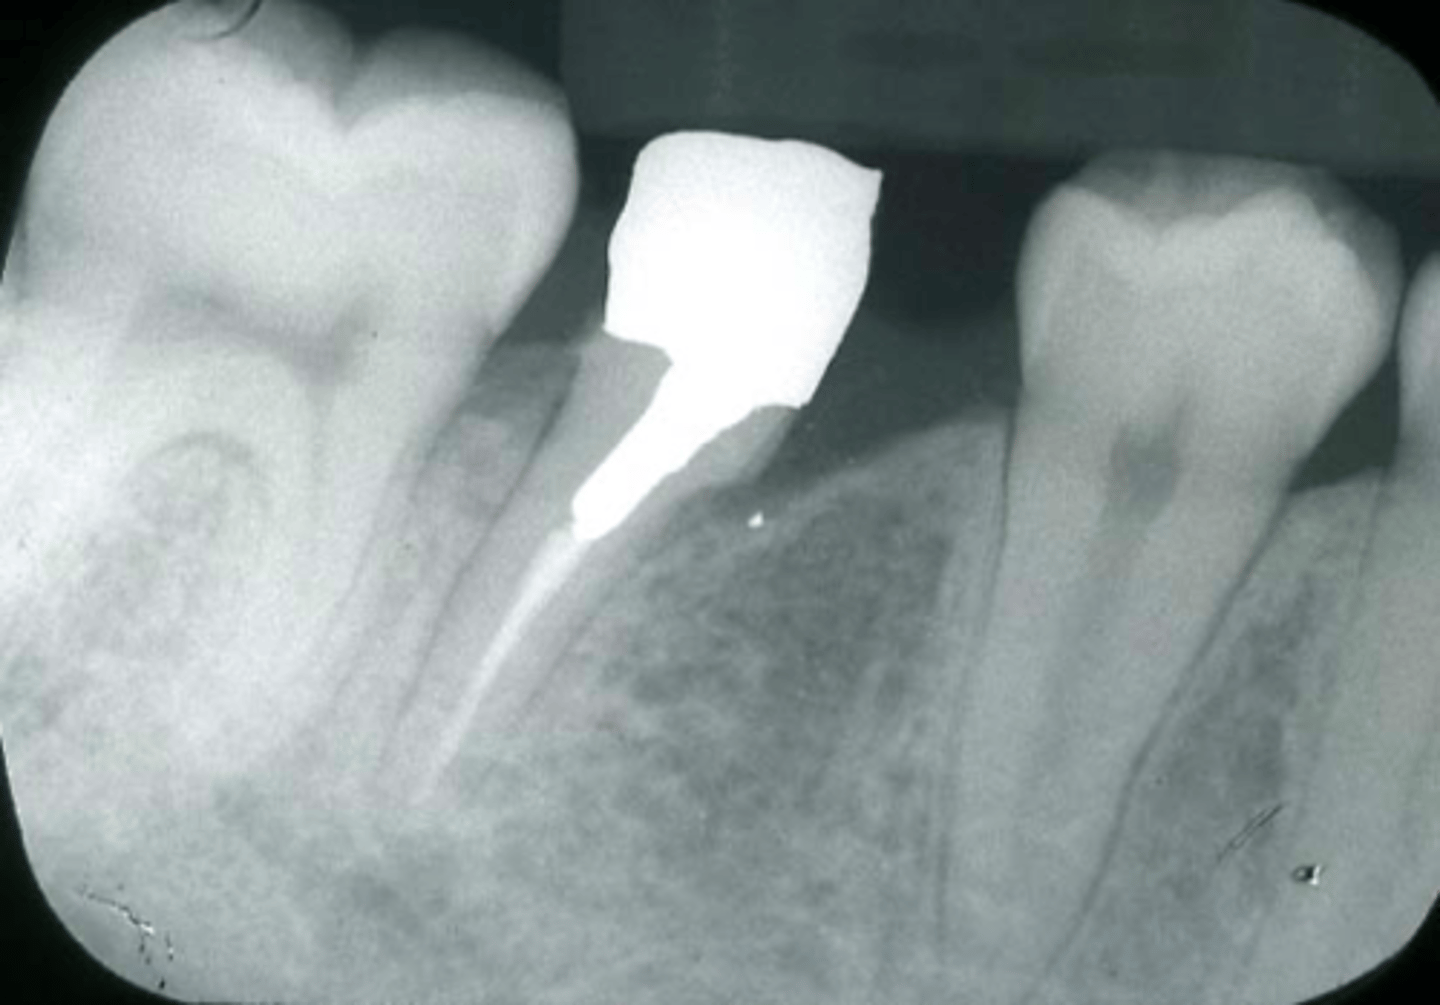

Infected silver point (Retreatment should be attempted first)

What is the cause of this apical radiolucency?